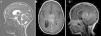

Atypical teratoid rhabdoid tumors (AT/RT) of the central nervous system are rare, very aggressive embryological tumors, typically diagnosed in young patients and having a low survival rate after diagnosis. The aim of this study was to emphasize, based on the latest results in the literature, the need for protocols for multidisciplinary treatment in these patients.

ResultsTwo of our 3 cases (supratentorial and spinal tumors) did not show any progression of the disease after long follow-up, in contrast with most of the cases available in the literature. The second patient had a shorter survival.

ConclusionsPatient age at the time of diagnosis, supratentorial location of the mass and fewer complications with adjuvant treatments seem to be factors yielding good prognosis for AT/RT tumors. In agreement with the latest international protocols, multidisciplinary treatment is the ideal treatment, consisting of radiotherapy and chemotherapy after complete tumor resection.